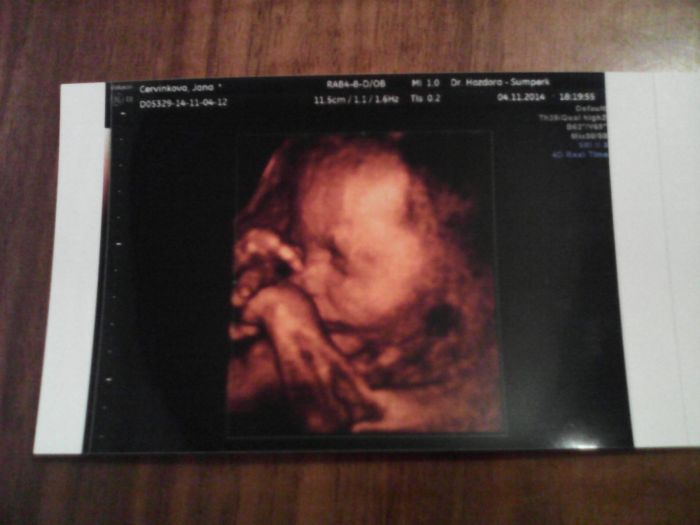

Včera jsem byla na genetickém ultrazvuku. 29+1tt,Marjánka váží 1341gr,vše je v naprostém pořádku a zaujala polohu hlavičkou dolů. Já úspěšně kynu. Mám nahoře 8kilo,ale připadám si jako hrošík liberyjský. Nastávající tatínek taky kyne se mnou. Filda se těší na malou sestřičku.Přikládám další fotky.